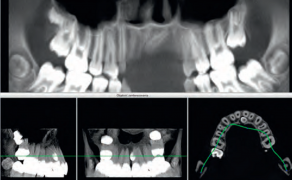

STRESZCZENIE: Rehabilitacja protetyczna z użyciem implantów w strefie estetycznej jest jednym z najbardziej wymagających zadań w stomatologii implantologicznej. Uzyskanie optymalnego efektu estetycznego stawia przed lekarzem klinicystą ogromne wyzwanie. Stworzenie atrakcyjnej odbudowy implantologicznej w strefie estetycznej opiera się na szczegółowym planie leczenia. Wynik estetyczny zależy od aspektów chirurgicznych i protetycznych. Aspekty chirurgiczne obejmują prawidłowe ułożenie platformy implantu w trzech kierunkach i udane zachowanie lub odtworzenie ściany kości przedsionkowej o odpowiedniej wysokości i grubości. Aspekty protetyczne obejmują jakość samego uzupełnienia oraz tworzenie otaczających je tkanek miękkich okołoimplantacyjnych, czyli profilu wyłaniania, które harmonizują z sąsiadującym uzębieniem.

SUMMARY: Prosthodontic rehabilitation with implants in the aesthetic zone is one of the most demanding tasks in implant dentistry. Obtaining an optimal aesthetic effect poses a great challenge to a clinician. Creating an attractive implant reconstruction in the aesthetic zone is based on a detailed treatment plan. The aesthetic result depends [...]